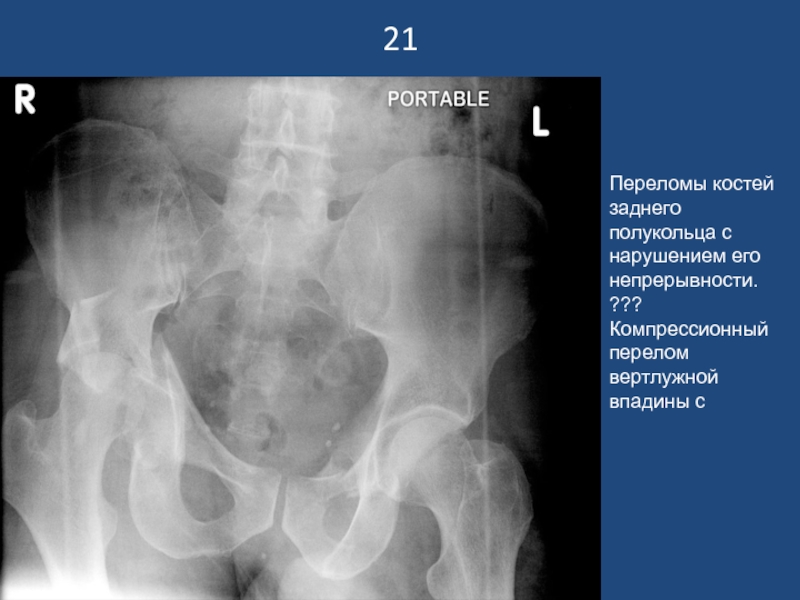

Слайд 2221

Переломы костей заднего полукольца с нарушением его непрерывности. ???Компрессионный перелом

вертлужной впадины с

21Переломы костей заднего полукольца с нарушением его непрерывности. ???Компрессионный перелом вертлужной впадины с